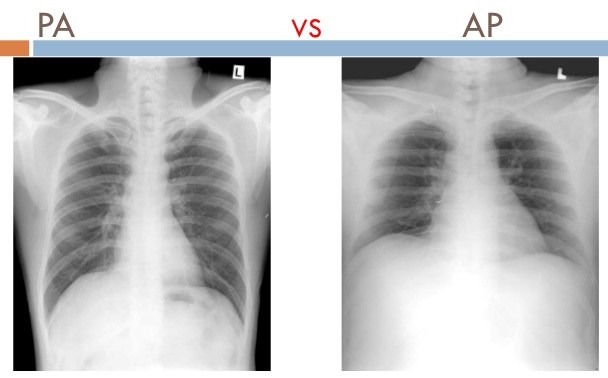

Posteroanterior View (PA)

A standard view for chest X-rays taken with the X-ray beam directed from posterior to anterior.

Anteroposterior View (AP)

A chest X-ray view taken with the X-ray beam directed from anterior to posterior.